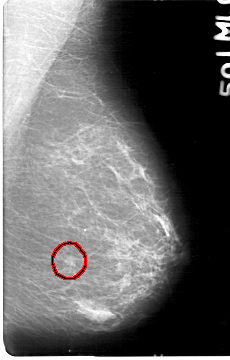

D_4047_1.LEFT_CC

FILE: D_4047_1.LEFT_CC.OVERLAY

TOTAL_ABNORMALITIES 1

ABNORMALITY 1

LESION_TYPE MASS SHAPE OVAL MARGINS OBSCURED

ASSESSMENT 0

SUBTLETY 4

PATHOLOGY BENIGN

TOTAL_OUTLINES 1

BOUNDARY